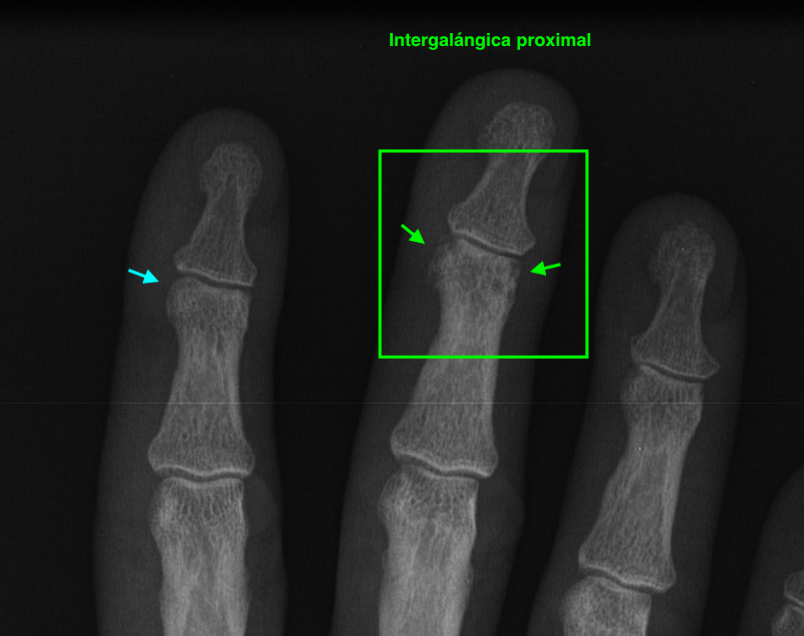

Principalmente dos. En los dedos, concretamente en las articulaciones interfalángicas, la proximal y la distal de los dedos segundo a quinto, hemos visto en numerosas ocasiones esos dedos retorcidos en esas articulaciones, en la metarpolángica, también, por supuesto, pero nos vamos a quedar con las interfalángicas. Cuando el avance de la enfermedad es muy importante, la mano está muy deformada, pero cuando estos síntomas comienzan podemos ver que solo algunas de estas articulaciones comienzan a cambiar.

El paciente puede notar como sus articulaciones empiezan a inflamarse, como si tuviera pequeños bultitos o nódulos en esas articulaciones. Si esos cambios con aspecto de bultos se dan en las articulaciones intefalángicas distales, estaremos frente a los conocidos como Nódulos de Heberden y si estas primeras deformaciones apareciesen en las interfalángicas proximales, se denominarían Nódulos de Bouchard.

Flecha azul, normalidad, flecha verde, patología.